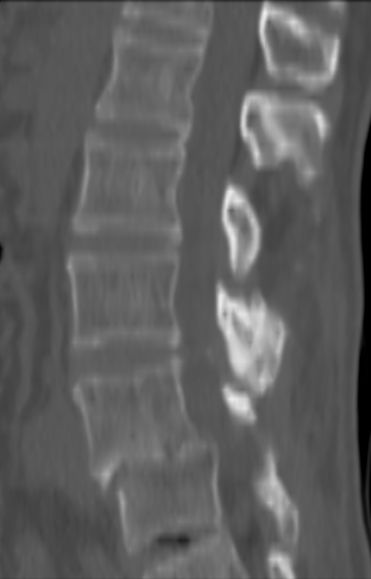

以下是引用余辉在2007-9-4 21:00:00的发言:[br]椎体棘突有点异常(像是被切割了),不知有否手术史,如椎体融合术等。单纯的退行性变可以出现椎间隙变窄,但同时一般会出现椎体上下缘的硬化增生,且椎体间完全融合的机率更小,本例椎体完全融合且椎体上下皮质缘破坏掉了,如果没有手术史,就应该考虑椎间盘炎性病变了,且椎体棘突及棘间韧带的变化也并不是不支持这个,多数小关节也融合了,且其形态也容易让人联想到如强脊炎及类风关等病变。[br][br][本贴已被 余辉 于 2007-9-4 21:03:55 修改过]

以下是引用chry3在2007-9-4 20:42:00的发言:[br]椎间盘病史?是什么样的病史,无双下肢放射痛,那就不是椎间盘突出了。是感染、什么性质的?[br]从图象看椎间隙消失,椎间盘组织未见,锥体滑脱是因为椎间盘溶解造成的[br]l4、5椎体骨质结构未见异常,l5上缘是l4的长期压迫所致[br]还是考虑椎间盘感染,结核。[br]